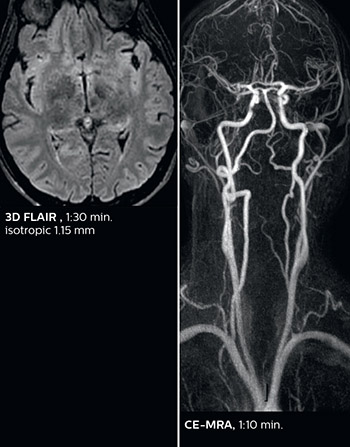

“Some routine exams that we use every day have been shortened since we started using Elition. For example, we now use mostly a comprehensive stroke protocol (high b-value diffusion, fast 3D FLAIR, TOF, supra-aortic vessels angiography, SWIp, T1 post gad) that lasts 10 to 11 minutes, but our fast stroke protocol takes only 7 minutes. Our routine IAC needs about 10 minutes scan time and our comprehensive brain MS examination requires no longer than 13 minutes of scan time. Our ability to reduce acquisition times of most sequences helps to shorten total examination times, which in turn helps us to increase the number of patients we scan per day.

“The fast scanning capabilities that came with Elition allow us to do a really quick examination and answer a lot of questions within a short time. We use every tool available to accelerate image acquisition while maintaining a reasonable image quality. So, for most of the sequences we use Compressed SENSE, for example, in our 3D FLAIR, in contrast-enhanced and noncontrast MR angiography, and for susceptibility-weighted sequences.”

Dr. Savatovsky appreciates the improvements and flexibility that Elition with Compressed SENSE and MultiBand SENSE provides, particularly for stroke patients. “For stroke, it allows us to cut about 5 minutes off of our stroke protocol, or to keep the same acquisition time and get more insights.”

The ability to perform more sequences can help in making a swift and confident diagnosis. “For example, our stroke cases usually include the regular sequences that every center does (b1000 diffusion, FLAIR, time-of-flight angiography), but we also image supra aortic vessels, and we can replace a gradient echo sequence with a fast 50-second susceptibility-weighted sequence, and all of this doesn’t add much time. because all the regular sequences are accelerated on Elition.”

Fast acute stroke protocol

This is an example of acute ischemic stroke with distal occlusion of the right posterior cerebral artery. Note the improved visibility of the ischemic territory on the diffusion weighted image with high b-value. The 3D FLAIR shows a distal PCA occlusion. The fast SWIp depicts the thrombus on the isolated second echo image. The total scan time (including SmartBrain, preparations and a fast 3D T1w TSE Gd) is 8:00 minutes.